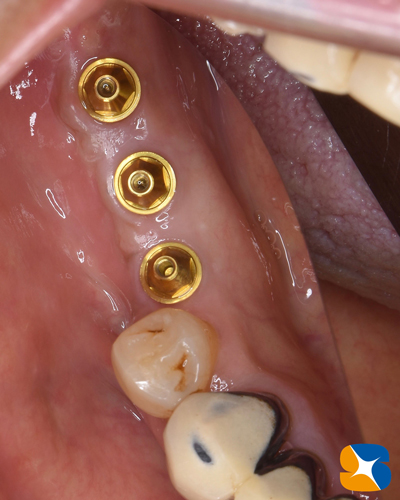

奈良 生駒 石切 インプラント 寝ながら無痛インプラント 良心価格 10年保証 再生医療 まず、CT画像で現状を伝え、充分な治療計画を元にカウンセリングした結果、インプラント施術を行うことになりました。緊急手術のため今回は、技工士さんに依頼した手作りサージカルガイド(手術用のナビゲーション:無料)を使用しました。

奈良 生駒 石切 インプラント 寝ながら無痛インプラント 良心価格 10年保証 再生医療 3本のインプラント移植抜歯穴に人工骨とCGFを混ぜ合わせて埋めた「骨の再生治療(無料)」も同時に行いました。